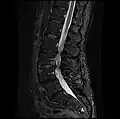

MRI lumbar spine post-hemilaminectomy (sagittal T2 FRFSE)

-

MRI lumbar spine post-hemilaminectomy (sagittal T1 FSE)